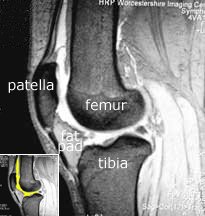

Note the relationship of the fat pad to the patellar tendon, and hence the extensor mechanism. It fills the space from the patellar tendon all of the way to the cruciate ligaments. In fact, it also extends sideways, making the bulge that one can often see in a normal knee on either side of the patella (red arrow). Normally the fat pad is not attached to either the meniscus or the patella, and is separated from the patellar tendon by the deep infrapatellar bursa.

With arthrofibrosis fat pad the fat pad becomes thickened and fibrosed, and the deep infrapatellar bursa can be obliterated. The fat pad can become adherent to the anterior horn of the meniscus and to the patella, and via the obliteration of the deep infrapatellar bursa it becomes adherent to the patellar tendon also. This thickened fat pad may also become tethered to the intercondylar notch where the cruciate lies.

Note also from the MRI that the fat pad is truly in contact with the bony lower edge of the patella. If that fat pad is scarred and contracted, can you imagine how it can pull the patella downward?

On the left, the inset MRI scan shows the extent of the suprapatellar pouch (yellow). In the large image, it shows up as white. Note how far this pouch extends above the patella. The fat pad is touching the patella and anterior part of the meniscus but is normally not adherent to these structures.